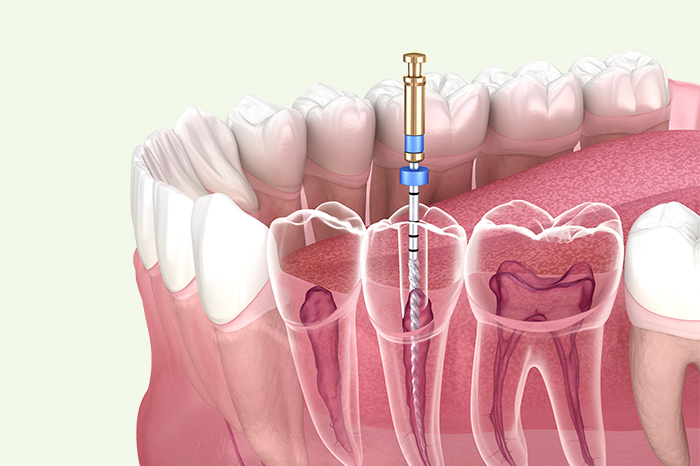

原因に向き合う根管治療

根管治療は、むし歯が進行し、歯の神経まで達した場合に行う重要な治療です。瑞穂区弥富にある当院では、痛みの原因を丁寧に見極め、歯をできる限り残すことを目的とした根管治療を行っています。ズキズキする痛みや、噛むと違和感がある症状も、根の中に原因が隠れていることがあります。症状だけに捉われず、将来を見据えた治療計画をご提案いたします。

精度を上げるための設備

歯の根の形や病変の位置を立体的に把握します。肉眼やレントゲンではわかりにくい根管の状態まで確認でき、治療計画の精度向上につなげています。

柔軟性が高く、複雑に曲がった根管にも対応します。根の形状に沿って処置できるため、無理な削りを防ぎ、精度の高い清掃を行います。

治療する歯のみをゴム製シートで隔離し、唾液や細菌の侵入を防ぎます。清潔な状態に保つことで、再感染のリスクを抑え、安定した治療結果を目指します。

根管内を均一に拡大・清掃します。回転数や動きを細かく管理することで、処置のムラを抑え、安定した根管治療につなげています。